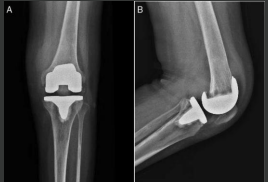

Sensor for Early Detection of Post-Surgical Infection (2022-110)

Technology Overview

Background